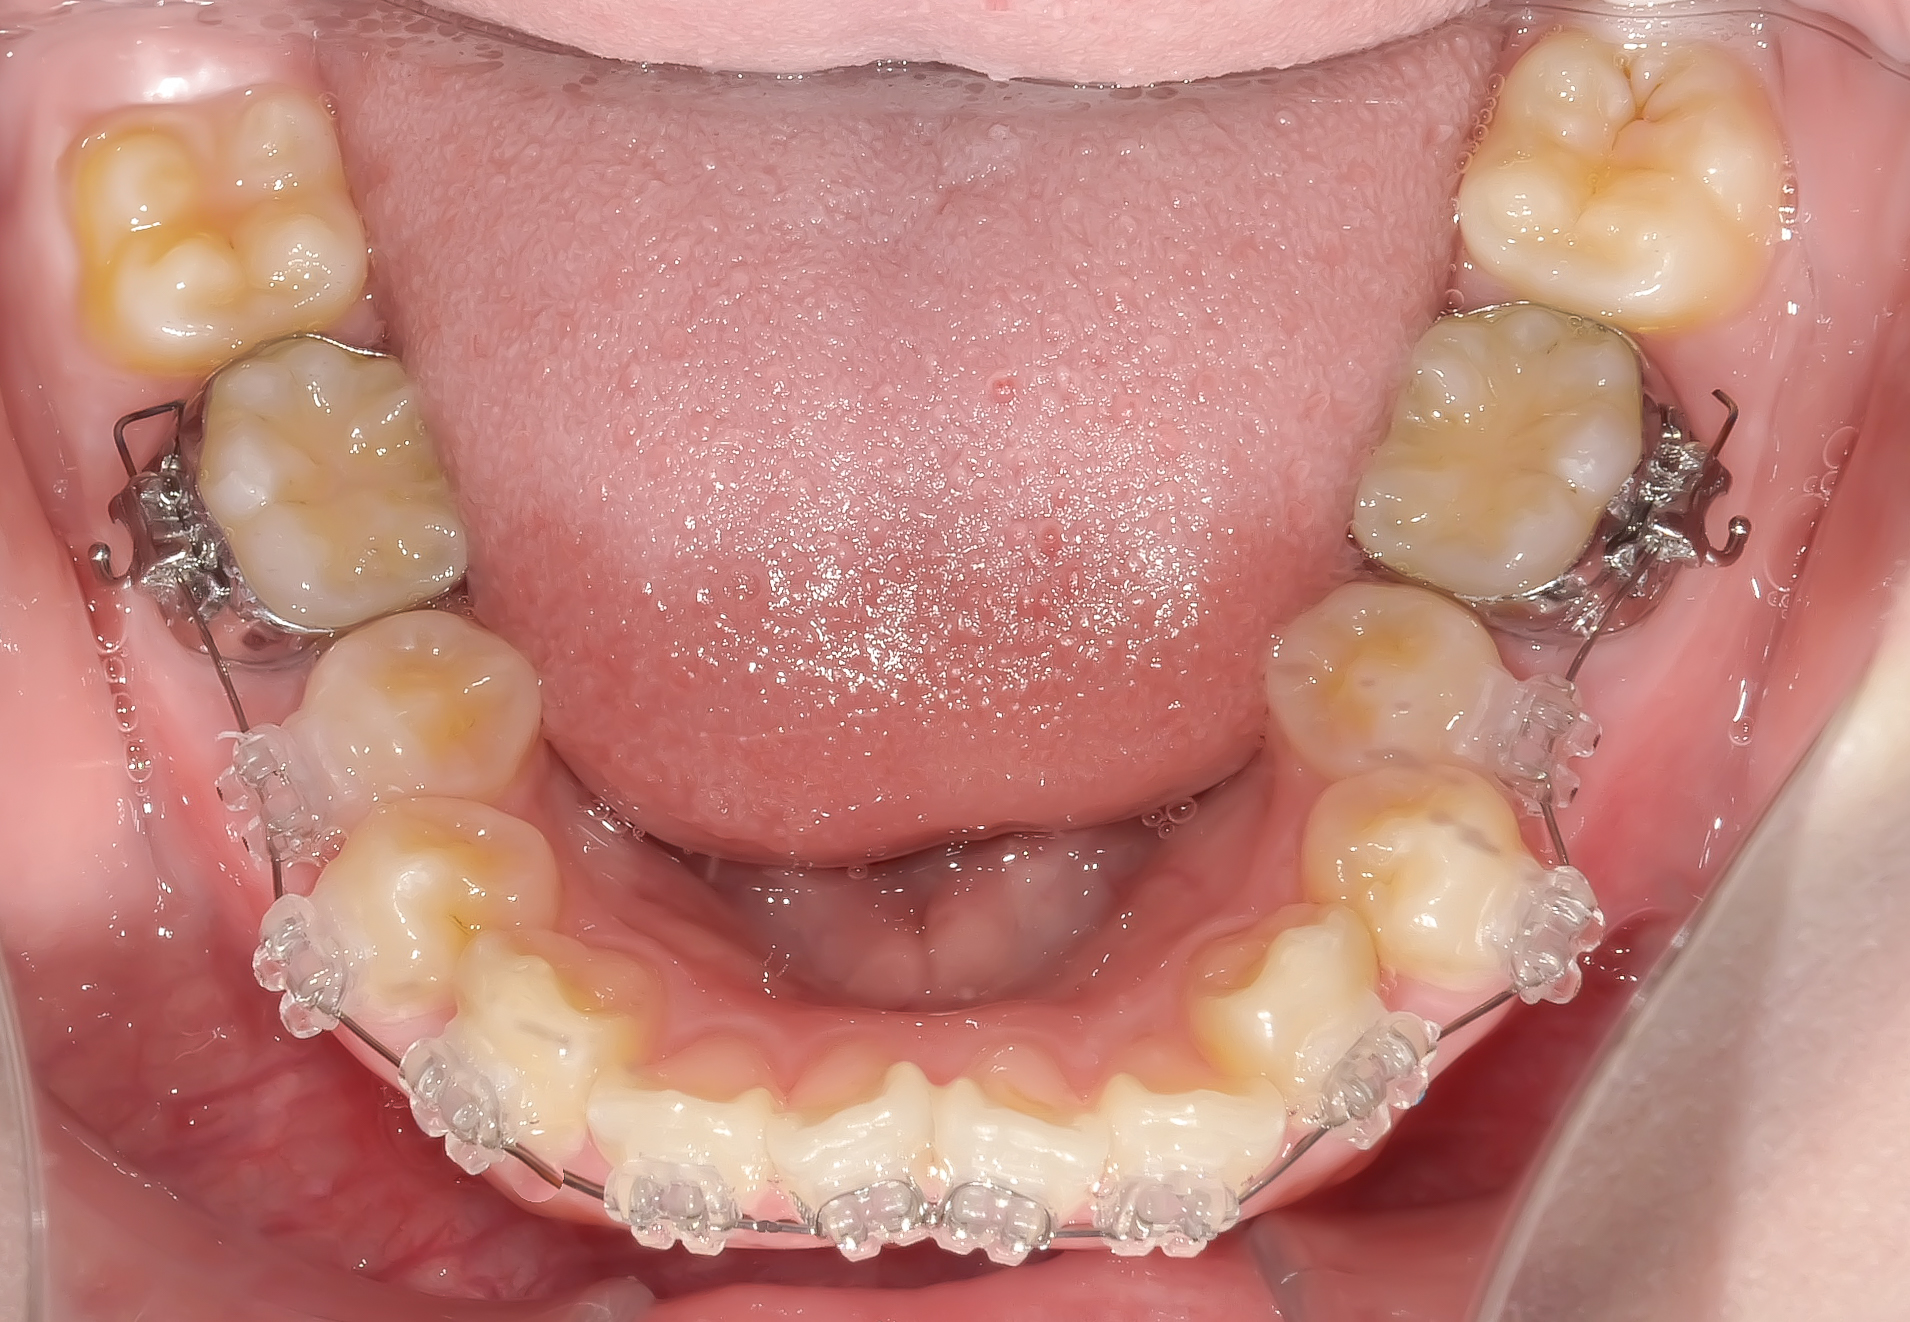

上顎に装置を装着した状態。

左右の前から4番目の歯を抜き、前歯を中に入れるスペースメイクを行います。

ワイヤーの超弾性(元の形に戻ろうとする力)が歯を並べます。